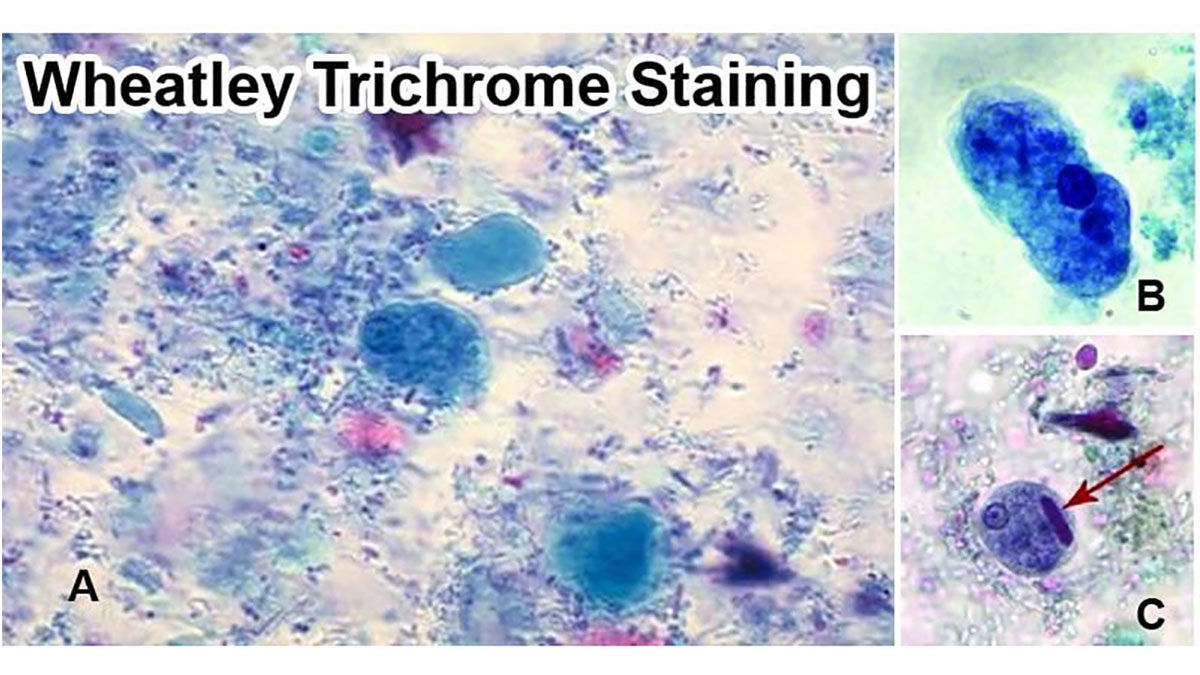

نتایج رنگ آمیزی تریکروم ویتلی به صورت زیر خواهد بود:

- مشاهده پروتوزوآها: تروفوزوئیتها و کیستهای پروتوزوآ باید زیر میکروسکوپ بررسی شوند.

- رنگآمیزی سیتوپلاسم تروفوزوئیتها: معمولاً آبی-سبز یا بنفش روشن دیده میشود.

- رنگآمیزی کیستها:کیستها رنگ بنفشتر دارند.

- مشاهده سلولهای انسانی و مخمر: سلولهایی مانند گلبولهای قرمز (RBCs)، پلیمورفونوکلئرها (PMNs)، ماکروفاژها و همچنین مخمرها میتوانند شناسایی شده و به رنگ قرمز دیده شوند.

- هستهها و اجسام داخل سلولی: هستهها و inclusion bodies نیزرنگ قرمز با تهرنگ بنفش به خود میگیرند.

- پسزمینه : پسزمینه رنگ سبز دارد و این باعث کنتراست بالا با پروتوزوآها میشود.

- گلیکوژن: مولکولهای گلیکوژن توسط حلالهای رنگ حل میشوند و به صورت شفاف و بدون رنگآمیزی دیده میشوند، درست مانند خود ارگانیسم.